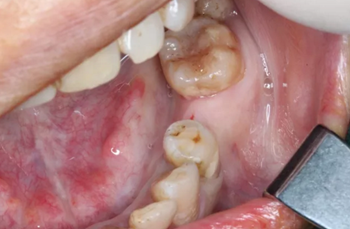

病例概述:48歲女性患者,口內(nèi)健康狀況良好,#35缺失多年,牙槽嵴頂骨寬度較窄。

#35缺失多年,導(dǎo)致#34向#35傾斜。

臨牙間距不足,因此,對種植體的位置要求極高。